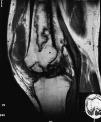

En junio de 1999 presenta dolor en articulación sin relación con el ejercicio, por lo que se realiza resonancia magnética nuclear (RMN), encontrándose los hallazgos radiológicos descritos en la fig. 1.

Figura 1. Cortes sagitales de rodilla derecha en secuencias potenciadas en T1 y T2. Imágenes de morfología irregular en región diáfiso-metafisaria del fémur compatibles con infartos óseos. Además se observan erosiones subcondrales sugestivas de necrosis avascular. Abundante derrame articular.

La RMN es la técnica no invasiva más sensible para el diagnóstico de necrosis avascular5. Los hallazgos más típicos fueron una o varias áreas de hiposeñal en la porción subcondral del cóndilo femoral y/o del platillo tibial en secuencias potenciadas en T1 y T2.

Estos hallazgos pueden encontrarse en tres tipos de pacientes: traumatismo previo, enfermedad predisponente (lupus, uso crónico de esteroides y trasplantados renales) y ancianos sin ninguno de los factores de riesgo descritos. Hay algunas diferencias en la osteonecrosis (ON) espontánea o primaria y aquella que se desarrolla en pacientes con factores de riesgo (ON secundaria). Así, en la ON de rodilla en aquellos pacientes con LES, trasplante renal o uso crónico de esteroides, la afectación es bilateral en el 50% y afecta al cóndilo lateral en el 60%. En la forma primaria la afectación es unilateral e incide en cóndilo femoral y platillo tibial mediales6.